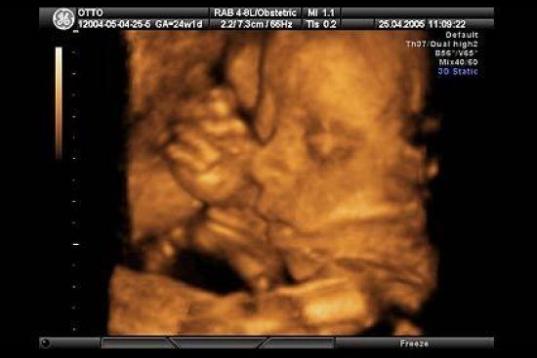

En esta galería puedes ver en fotos como es el desarrollo de un feto de semana en semana:

Desarrollo del feto, en fotos

Ver la galería